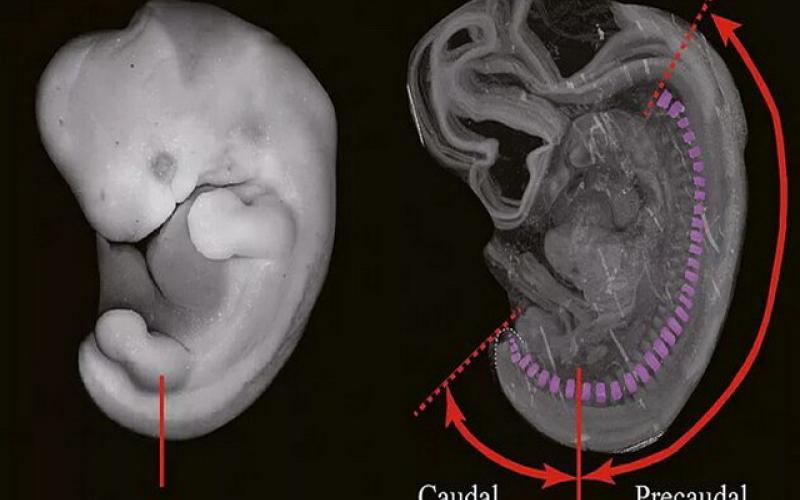

هنگامی که جنین انسان در رشد خود به حدود پنج هفتگی می‌رسد ساختار دم‌مانندی متشکل از لوله عصبی و «طناب پشتی» که به نوعی شبیه نخاع اولیه است، از بدن او جوانه می‌زند. هرچند این ساختار دم‌مانند در هفته هشتم رشد معمولاً دوباره جذب بدن جنین می‌شود، با این حال در برخی مواقع نادر این زائده جذب نشده و می‌تواند نشان‌دهنده وجود یک نقص مادرزادی بزرگتر باشد.